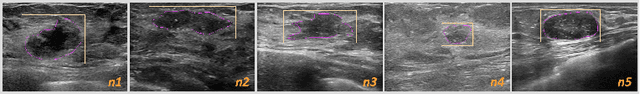

Abstract:Ultrasound is a vital diagnostic technique in health screening, with the advantages of non-invasive, cost-effective, and radiation free, and therefore is widely applied in the diagnosis of nodules. However, it relies heavily on the expertise and clinical experience of the sonographer. In ultrasound images, a single nodule might present heterogeneous appearances in different cross-sectional views which makes it hard to perform per-nodule examination. Sonographers usually discriminate different nodules by examining the nodule features and the surrounding structures like gland and duct, which is cumbersome and time-consuming. To address this problem, we collected hundreds of breast ultrasound videos and built a nodule reidentification system that consists of two parts: an extractor based on the deep learning model that can extract feature vectors from the input video clips and a real-time clustering algorithm that automatically groups feature vectors by nodules. The system obtains satisfactory results and exhibits the capability to differentiate ultrasound videos. As far as we know, it's the first attempt to apply re-identification technique in the ultrasonic field.